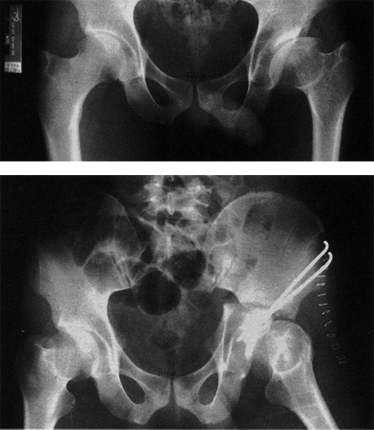

수술방법으로는 내반 및 외반 절골술, 굴곡 및 신전 절골술, 회전 절골술 등이 있으며, 고관절에 주요 근육인 외전근의 기능을 호전시키기 위한 대전자 이전 절골술이 있습니다. 대개 2가지 이상의 각변형을 교정하는 3차원적 교정이 필요한 경우가 많아 내반/외반 절골술과 함께 신전/굴곡 절골술이나, 회전 절골술을 같이 시행하기도 합니다. 내반/외반 절골술을 통해 관절면의 일치성이 증가됨을 볼 수 있습니다

고관절 주위 절골술 이미지